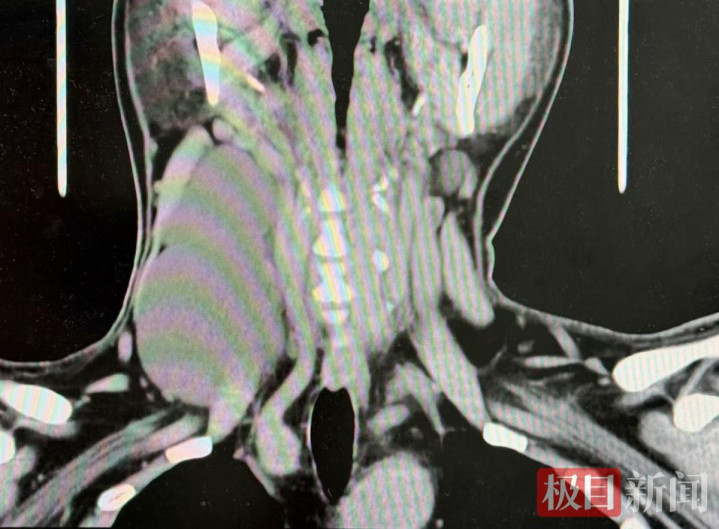

经详备检查,大夫发现这并非无为的颈部包块。影像学检查请示,李先生患有颈部庞杂占位性病变,且由于肿物的压迫,已导致其右侧颈内静脉顽固,出现缺血进展。值得瞩见识是,囊性淋巴管瘤是一种淋巴系统的良性病变,高发于儿童,在成年东说念主中极为荒僻。这一肿瘤不仅会严重影响颈部外不雅,导致颈部看成受限,正规配资网站更危境的是它会压迫颈部血管导致脑轮回不畅,出现头晕、头痛等不适症状。此外,由于囊性淋巴管瘤的瘤壁绝顶薄,一朝离散,淋巴液会在组织破绽内“游走”,极易激发更为不吉的纵隔感染,危及生命。

计划到病情的复杂性和进击性,甲状腺乳腺外科副主任医师张家铭、魏战杰携带团队为李先生制定了周详的手术有贪图。术中,大夫沿其颈侧联想了一个精确的斜行切口,在保护好周围要紧的神经和血管的前提下,注意翼翼地分离并好意思满取出了两枚隔离长达8厘米和7厘米的肿瘤。这两枚肿瘤内充满了清澈的淋巴液,宛如两颗弥散的“水球”。术后的病理检查效果证明,这两枚庞杂的肿瘤均为良性。流程一周的尽心照看和康复调整,李先生未出现并发症,颈部肿胀显然消退,当今已顺利出院。